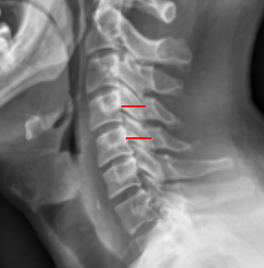

Image Type Cervical Spine X-Ray CT Scan MRI Scan Atlantodental Interval (ADI) Basion-Axial Interval Basion-Dens Interval (BDI) C2 Tilt C2–C7 Coronal Cobb Angle Cervical C2-7 lordosis C2-C7 Translation Chamberlain’s Line / McGregor’s Line Flexion-Extension George’s Line (Posterior Cervical Line) K-Line Interpedicular Distance (IPD) Occiput-C2 Angle Occipital Condyle–C1 Interval (CCI) Posterior Atlantodental Interval (PADI) Power’s ratio Sagittal Canal Diameter Sagittal Vertical Axis (SVA) Spinolaminar line Swischuk Line T1 Slope Torg/Pavlov Canal-to-Body Ratio